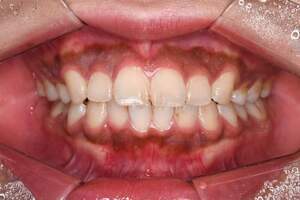

歯石除去、着色除去

| 年齢 | 25歳・女性 |

|---|---|

| 主訴 | 主訴:歯石除去、着色除去 治療部位:全顎 |

| 治療内容 | 初診検査・歯石除去・PMTC |

| 治療期間 | 60分 |

| 費用 | 合計約10,500円 初診検査約3,000〜4,000円 歯石除去約1,000円 PMTC5,500円(自費診療) (2024年6月現在) (歯の本数や検査内容で料金が変動します。) |

| リスク・副作用 | ・歯ぐきの炎症がある場合は歯石除去中に出血を伴う可能性があります。 ・処置後、知覚過敏が起こる可能性があります。 ・歯ぐきの炎症が治ると、歯ぐきが引き締まる為歯が長くなったと感じる事があります。 ・PMTCは歯を白くするものではなく着色・バイオフィルムの除去を目的としています。 |

| 治療方針 | 全顎的な歯石除去後、PMTCで着色とバイオフィルムを除去。 |

| 特記事項 | 矯正経験あり ホワイトニング経験あり |

| 担当者所見 | 歯石除去と前歯部の着色除去希望で来院されました。 下顎前歯の歯間部の歯石に対してフロス指導を行いました。 PMTCにより着色がなくなり、歯のトーンアップも感じられたと喜んでくださいました。 |